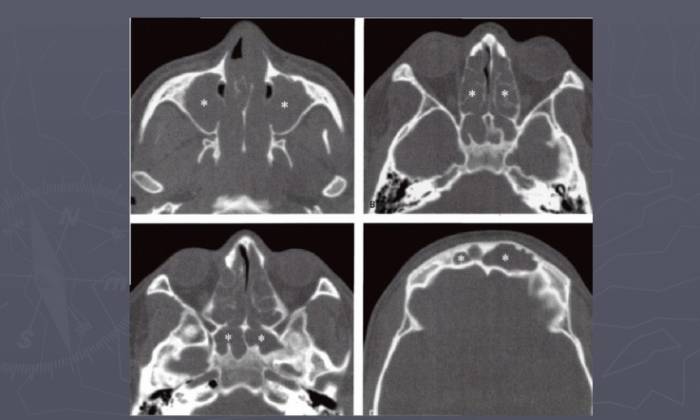

Проявление гайморита без сопутствующего насморка отличается от типичного воспаления околоносовых пазух появлением повышенного давления в гайморовом синусе. Своевременное проведение рентгенологического обследования и риноскопии поможет подозревать наличие блокировки верхнечелюстного отверстия.

При типичном течении гайморита температура начинает снижаться в процессе лечения антибиотиками примерно на второй день от начала терапии. Однако о полном выздоровлении можно говорить только тогда, когда показатели крови возвращаются к норме и рентгенологическое обследование не показывает наличие очага затемнения в пазухах. Нормальная температура восстанавливается на этапе утихания воспаления, при этом отсутствие лечения в этот период может вызвать повторное возникновение заболевания или переход в хроническую форму.